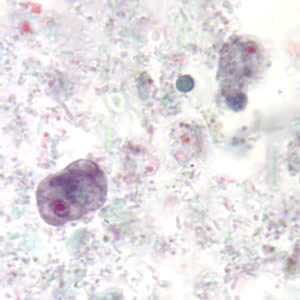

E. coli trophozoites stained with trichrome.

Figure A: Trophozoite of E. coli stained with trichrome.

Figure B: Trophozoite of E. coli stained with trichrome.

Figure C: Trophozoites of E. coli stained with trichrome.

Figure D: Trophozoite of E. coli stained with trichrome.